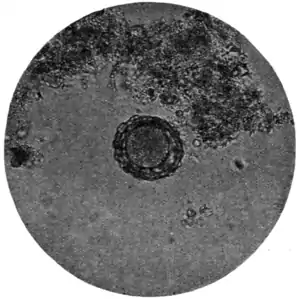

Fig. 171.—Ovum of A. lumbricoides, x 250. (Photograph by Dr. J. Bell.)